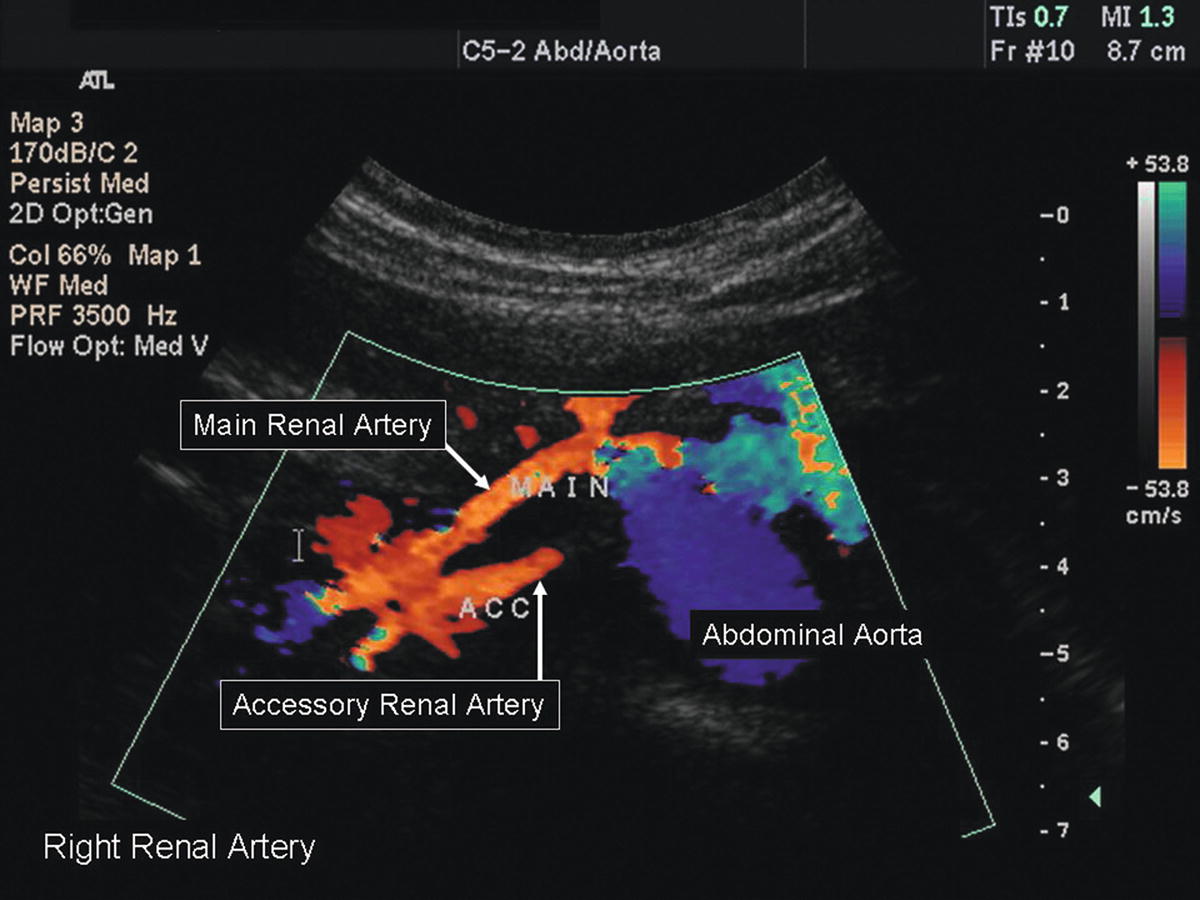

Accessory Kidney Ultrasound . ultrasound imaging is a key investigatory step in the evaluation of chronic kidney disease and kidney transplantation. accessory renal arteries originate from the abdominal aorta either above or below the main renal artery and reach the hilum. accessory renal arteries enter the kidney through the renal hilum, supply the superior and inferior renal poles, and have caliber similar to. the authors review anatomic variants and pathologic conditions of the renal arteries and veins, with a focus on us, ct, and mr imaging findings, and. a supernumerary kidney (sk) is an additional kidney with its own capsule and blood supply that is not fused with the. the supernumerary kidney especially on right side is a rare diagnosis. Only few case reports are documented in. most commonly accessory renal arteries arise from the abdominal aorta and supply the inferior pole of the kidney, although.

accessory renal arteries enter the kidney through the renal hilum, supply the superior and inferior renal poles, and have caliber similar to. ultrasound imaging is a key investigatory step in the evaluation of chronic kidney disease and kidney transplantation. the authors review anatomic variants and pathologic conditions of the renal arteries and veins, with a focus on us, ct, and mr imaging findings, and. the supernumerary kidney especially on right side is a rare diagnosis. a supernumerary kidney (sk) is an additional kidney with its own capsule and blood supply that is not fused with the. most commonly accessory renal arteries arise from the abdominal aorta and supply the inferior pole of the kidney, although. accessory renal arteries originate from the abdominal aorta either above or below the main renal artery and reach the hilum. Only few case reports are documented in.